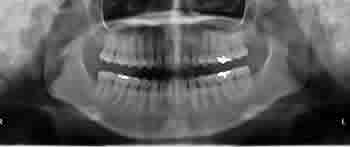

親知らず症例 ①

| 治療前 | 治療後 |